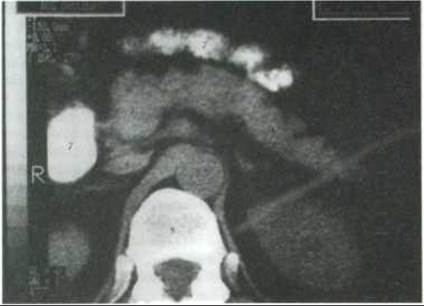

Комп’ютерна томографія (КТ) підшлункової залози. Комп’ютерна томографія - важливий інформативний метод досліджень, який дає достеменну інформацію про стан підшлункової залози, а також можливість краще оцінити морфо-функціональний стан суміжних органів (нирок, селезінки, жовчних шляхів, брижі, тонкої та товстої кишок).

Оптимальне зображення підшлункової залози отримують методом сканування на рівні Th XII—L II. Головка підшлункової залози на томограмах розміщена приблизно на рівні L І, а тіло і хвіст - вище на 1-2 хребці. Ознаками, які дають змогу оцінити розташування підшлункової залози та установити співвідношення з органами, що її обмежують (синтопія), є обриси верхньої брижової Артерії та судинної ніжки селезінки (рис. 269). На задній поверхні залози під артерією розташована селезінкова вена, діаметр якої перевищує діаметр однойменної артерії у 2 рази, вона краще визначається на комп’ютерних томограмах. Структура підшлункової залози у молодих людей гомогенна, а у літніх зменшена в розмірах і має часточкову будову. Заочеревинна клітковина, яка обмежує орган, дозволяє чітко візуалізувати підшлункову залозу.

Рис. 269. Комп’ютерна томограма заочеревинного простору на рівні підшлункової залози, нирок та наднирників (за О. Іванковим):

1 - підшлункова залоза; 2 - головка підшлункової залози; 3 - тіло підшлункової залози, 4 - хвіст підшлункової залози, 5 - черевна аорта, 6 - нирки; 7 - дванадцятипала кишка; 8 - Нижня порожниста вена; 9 - хребець